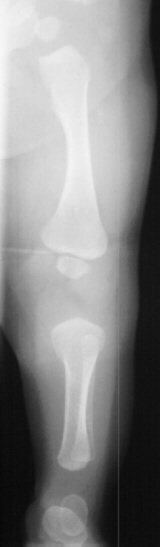

On x-ray the distal and middle phalangeal segments are shorter in relation to the proximal phalangeal segments.

The fibula is disproportionately shorter than the tibia .